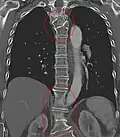

Block vertebrae

Block vertebrae occur when there is improper segmentation of the vertebrae, leading to parts of or the entire vertebrae being fused. The adjacent vertebrae fuse through their intervertebral discs and also through other intervertebral joints so that it can lead to blocking or stretching of the exiting nerve roots from that segment. It may lead to certain neurological problems depending on the severity of the block. It can increase stress on the inferior and the superior intervertebral joints. It can lead to an abnormal angle in the spine, there are certain syndromes associated with block vertebrae; for example, Klippel–Feil syndrome. The sacrum is a normal block vertebra.[8]

Congenital block vertebra of the lumbar spine. CT volume rendering. -

Congenital block vertebra of the lumbar spine. CT volume rendering.